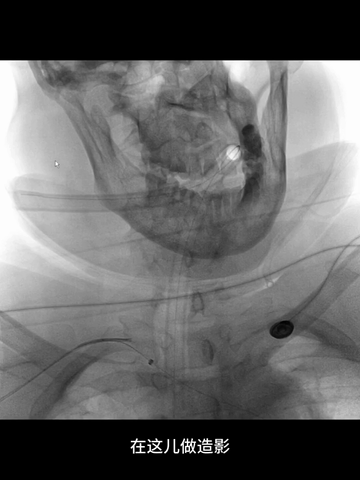

右股动脉穿刺置8F短鞘,5F长多功能管(125cm)和6F长鞘(90cm,Cook)组成同轴,导丝导引下5F管头端进入右锁骨下动脉。

长鞘跟进到右锁骨下动脉近端。

5F管沿导丝送至右腋动脉,经此管送入一.018"导丝(Command 18),其头端置于右肱动脉远端,保留导丝,交换出5F管,.018"导丝作悬吊支撑用。

微导管(Rebar 18)配合微导丝(Command 14)尝试超选右椎动脉,但微导丝头端难以通过V1的曲折管腔;后长鞘内衬一4F长多功能管增强支撑和指向性,但微导丝仍然难以克服右V1的曲折。

微导丝头端改塑形状后,还是克服不了右V1曲折。

穿刺右桡动脉,置入6F桡鞘;4F长多功能管(125cm)和Navien 072(105cm)组成同轴,泥鳅导丝导引下,4F管头端行至右锁骨下动脉近端。